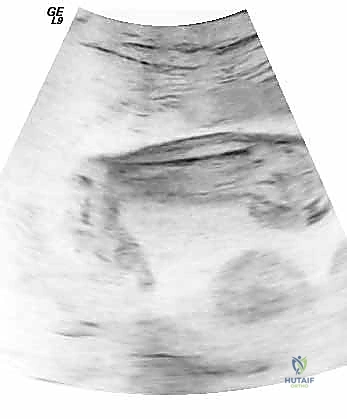

يمكن تشخيص القدم الحنفاء في كثير من الأحيان قبل الولادة، عادة في الأسبوع الـ 20 من الحمل عبر فحص الموجات فوق الصوتية (Ultrasound) الروتيني. هذا التشخيص المبكر يمنح الوالدين فرصة للبحث عن أفضل أطباء جراحة عظام الأطفال، مثل أ.د. محمد هطيف، للتشاور ووضع خطة العلاج التي ستبدأ فور الولادة.